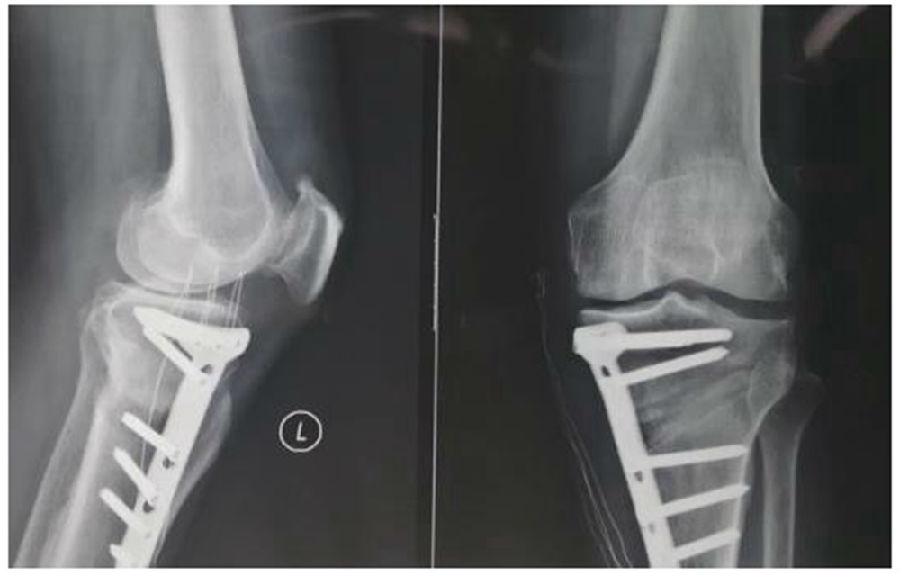

拉力钉复位,结构性植骨

左侧患者未植骨正常负重,术后4个月不愈合;右侧患者非结构性植骨过早负重,术后1年未愈合